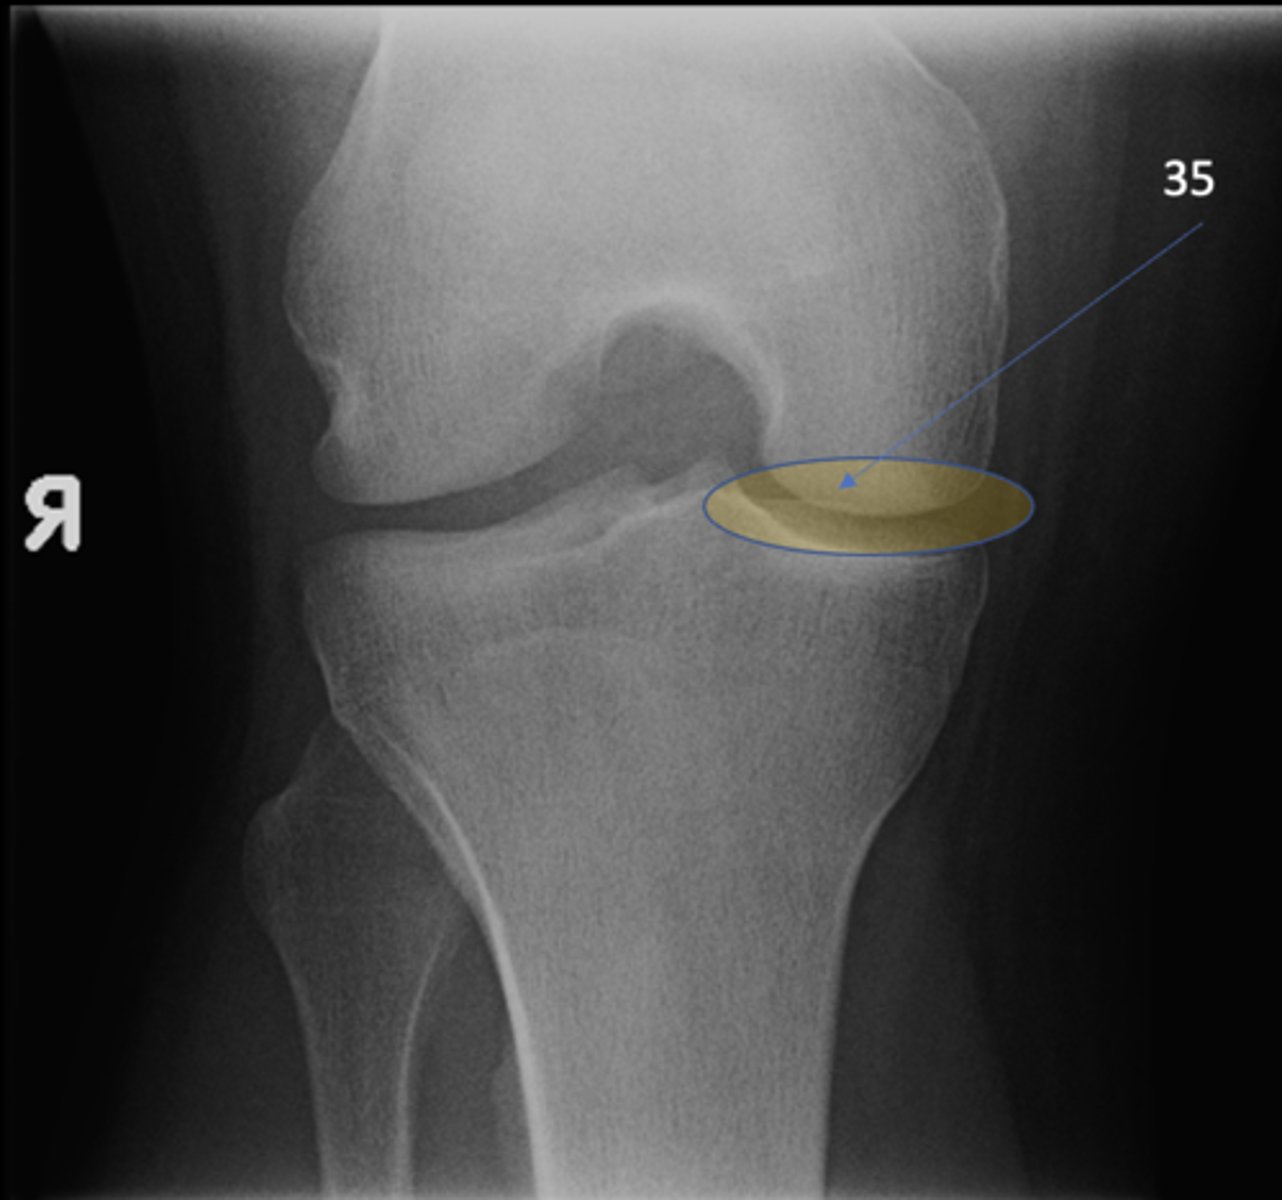

Medial tibiofemoral joint

ID 35 (joint)

<p>ID 35 (joint)</p>